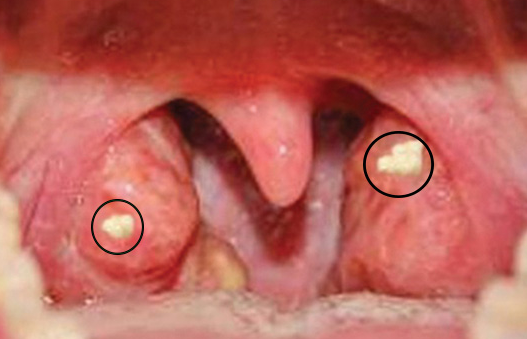

편도결석은 편도조직 내부에 생성된 작고 노란 덩어리로, 몇 밀리미터에서 몇 센티미터까지 다양한 크기로 나타나며, 주로 편도의 깊은 틈새에 자리 잡습니다. 이 결석은 불쾌한 증상을 동반하기도 하지만, 심각한 건강 위협으로 이어지는 경우는 드뭅니다. 그러나 편도결석은 구취를 유발하거나 삼키는 데 어려움을 줄 수 있어, 적절한 관리와 예방이 중요합니다.

편도결석은 의사의 시각적 검사나 추가적인 장비를 통해 쉽게 진단할 수 있으며, 이를 통해 적절한 치료 계획을 세울 수 있습니다.

(1) 임상 평가 : 환자의 증상을 확인하고 목을 시각적으로 검사해 결석 여부를 판단합니다.